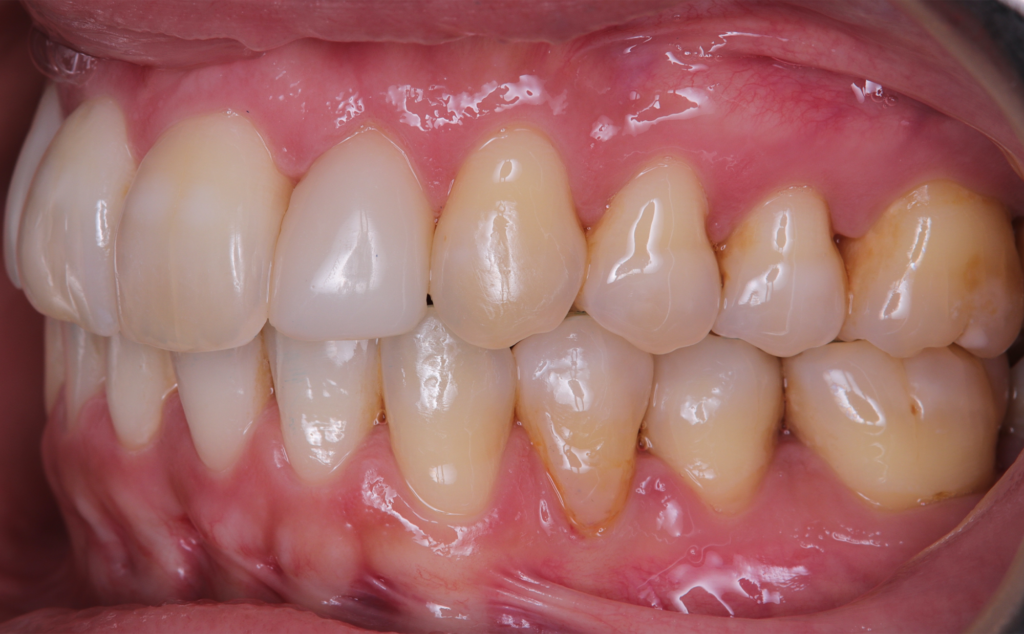

The patient, having completed a periodontal treatment phase, presented with significant aesthetic and functional concerns due to moderate crowding in both arches and a pronounced anterior crossbite. Clinical examination confirmed the need for comprehensive realignment, particularly in the anterior region. Although the patient had a history of periodontal issues, radiographic evaluation showed no signs of active disease. Based on these findings, the treatment plan was designed to carefully modulate orthodontic forces to protect the occlusion and surrounding tissues while addressing the misalignment.

Treatment plan and progress

To correct the misalignment and anterior crossbite without compromising tissue stability, a slower orthodontic treatment plan was devised using the Spark Advanced clear aligner system. The initial phase involved 36 aligners designed to gently expand and realign the dental arches, limiting the rate of tooth movement. Strategic interproximal reduction (IPR) was performed in the anterosuperior region (between teeth #21 and #11) to create the necessary space for proper alignment while avoiding excessive loading on the tissues.

To refine the results and enhance aesthetics, a second phase incorporating an additional 17 aligners was introduced. During this refinement stage, careful IPR in the lower arch helped harmonize the midline and achieve a balanced occlusion. Once satisfactory alignment was reached, provisional composite restorations were placed on the upper lateral incisors to aesthetically close any interproximal gaps.

A crucial aspect of the treatment was reducing the speed of tooth movement by 50%. This approach allowed a gradual application of orthodontic forces, giving the occlusion and tissues ample time to stabilize following the periodontal phase while effectively addressing the crowding and anterior crossbite.